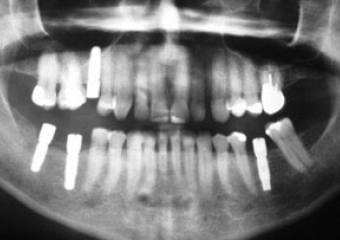

Raio X inicial